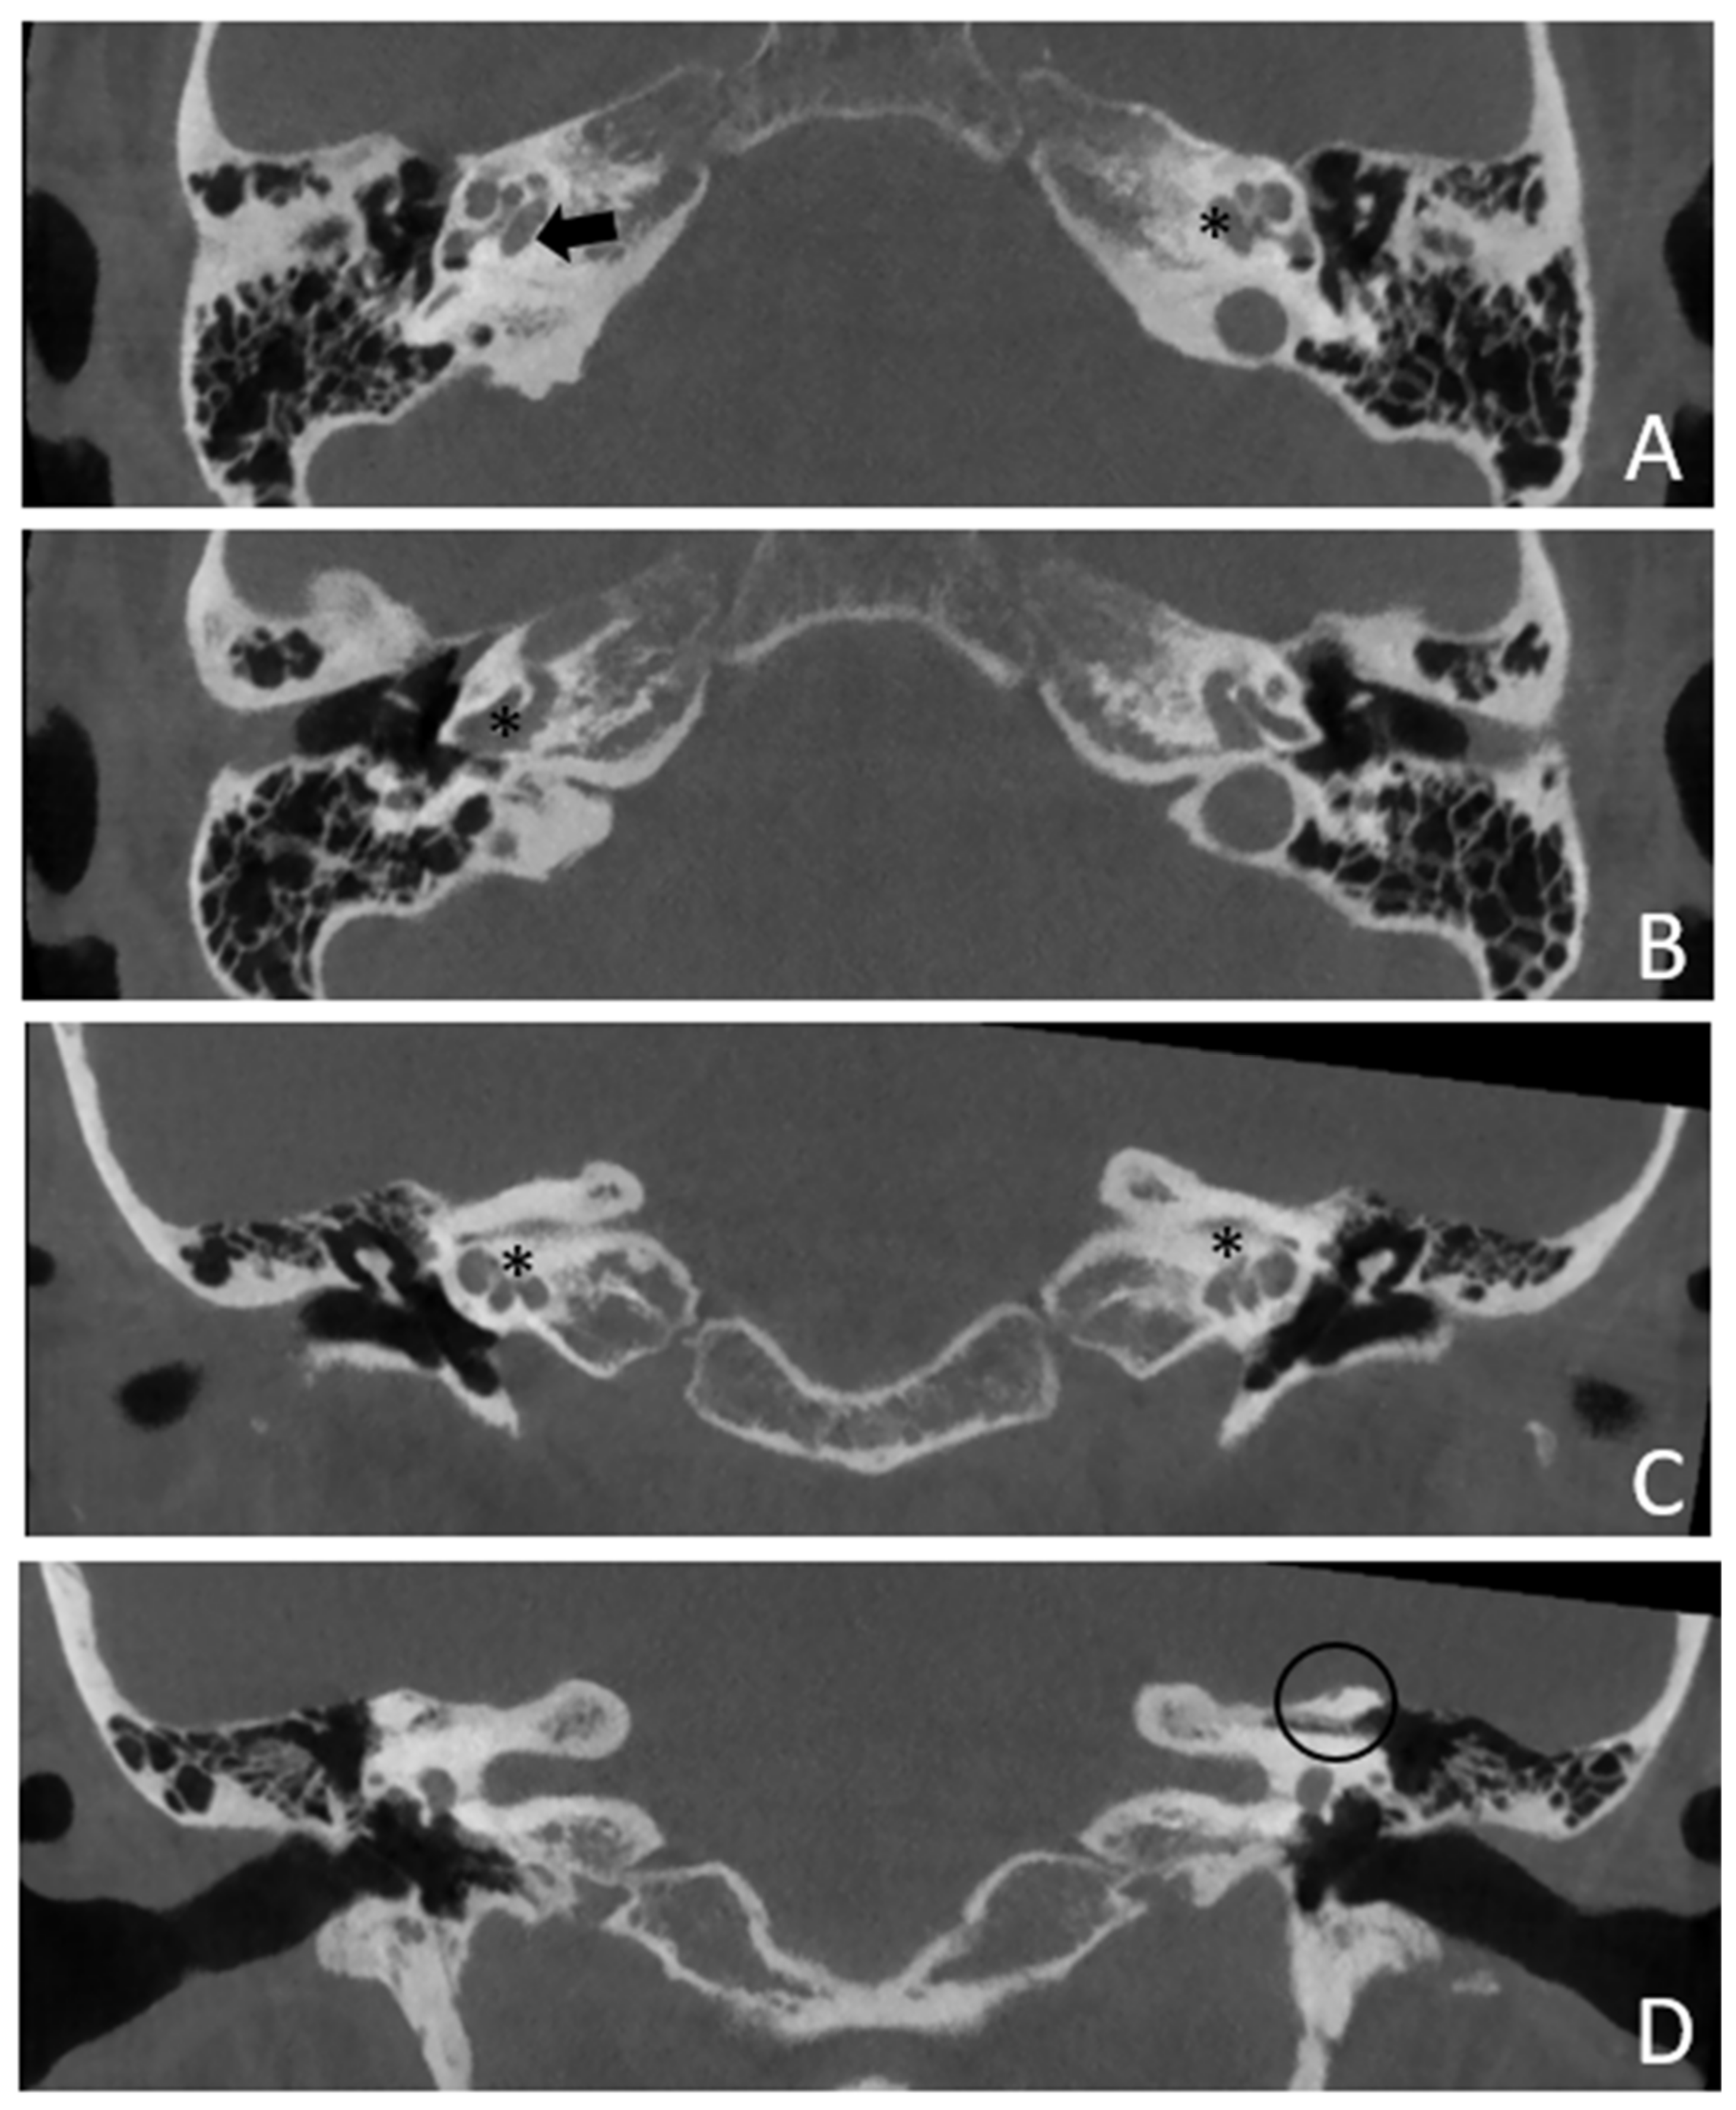

Patient #2, affected by OI-type I (COL1A1 mutation). MHL since diagnosis. Bone threshold was similar in both ears, but PTA was worse in the right ear with a larger ABG. HL progressed, but the difference between the two sides was maintained. The patient was fitted with conventional hearing aids bilaterally. Stapes surgery was not performed because of the radiological aspect (Figure 3 and Figure 4): a large cavity is present bilaterally and diffused communication between the cavity and the cochlea is evident.

Patient #3, affected by otosclerosis: HL started as mild CHL, but she had a progression with a worsening of the bone threshold, probably due to cochlear evolution of the disorder. Even in this case, there was no indication for stapes surgery because of the communication between CSF and perilymph through the cavities. The images also show a superior semicircular canal deiscence (SSCD)on the left. CT and MR images show the bilateral cavities (Figure 5 and Figure 6).

Figure 3. CT images of patient #2 with osteogenesis imperfecta. (A), axial plane; (B), coronal plane. A large pericochlear cavity is visible; arrows indicate its origin from the IAC, asterisks indicate the communication of the cavities with the cochlea.

Figure 5. CT images of patient #3 with bilateral otosclerosis and SSCD of the left ear. (A,B), axial plane; (C,D), coronal plane. A cavitating osteorarefation around the cochlea is clearly visible. The communication of the cavity with the cochlea is indicated by asterisks. The arrow indicates the origin of the cavity from the IAC. The circle indicates the dehiscence of the SSC on the left side.